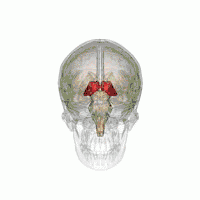

Visual depiction of basic thalamus